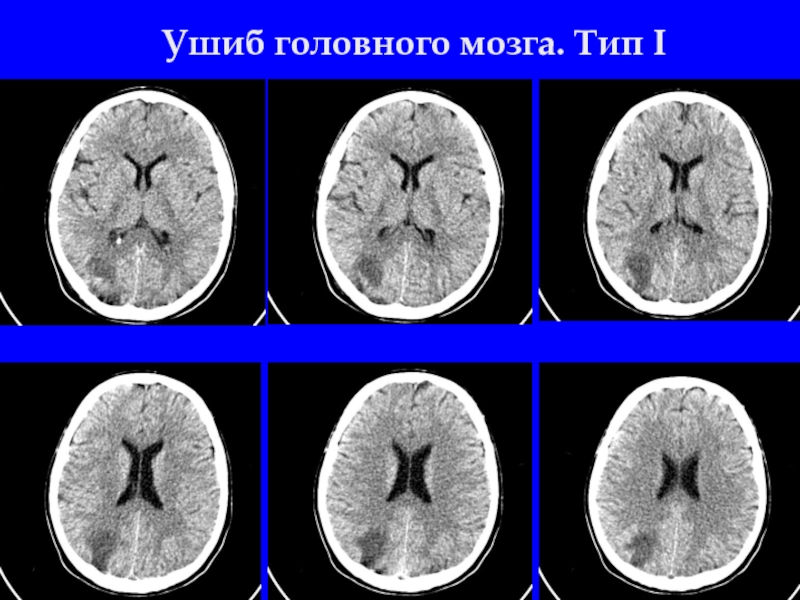

Слайд 3Ушиб головного мозга. Тип I